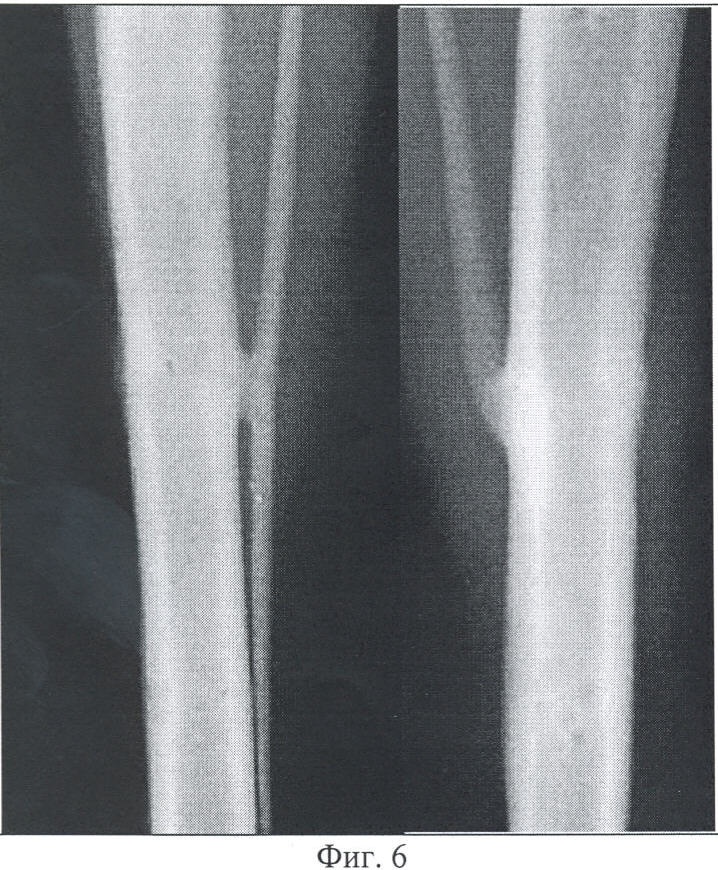

Фиг.6 – копия рентгенограммы костей голени согласно изобретению, 30 суток после прекращения фиксации аппаратом.

Через 1 месяц после снятия аппарата рентгенологически ось кости правильная. Линия излома не определяется. Сформирована единая костномозговая полость. Эндостальная реакция визуально не выявляется. Компактизированные периостальные напластования протяженностью до 0,6 см имеют толщину не более 1,0 мм (Фиг.6).